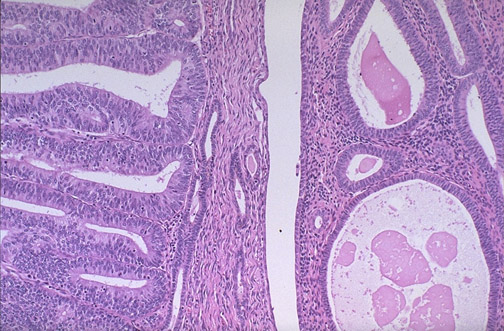

| The endometrial adenocarcinoma in the polyp at the left is moderately differentiated, as a glandular structure can still be discerned. Note the hyperchromatism and pleomorphism of the cells, compared to the underlying endometrium with cystic atrophy at the right. |